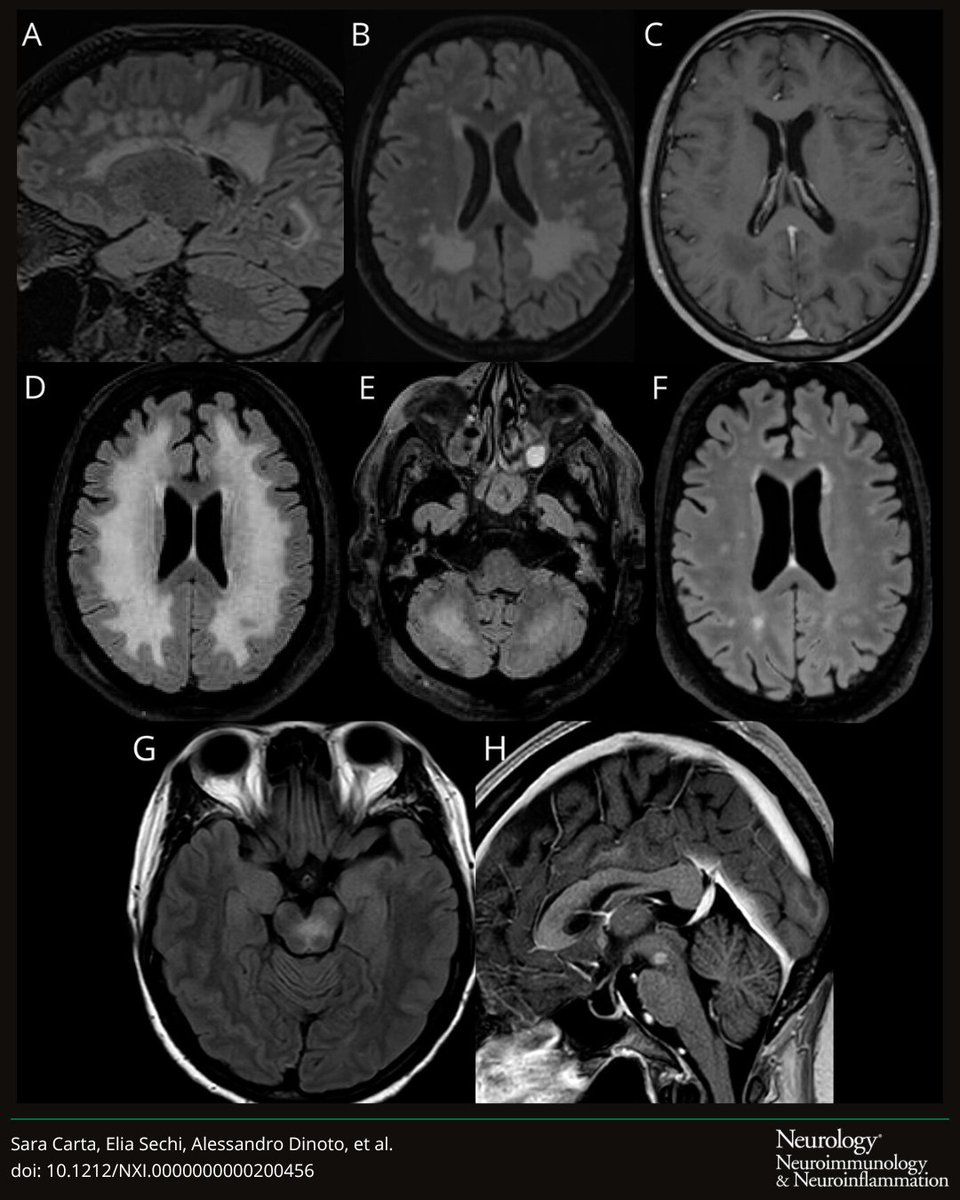

@EliaSechi

Elia Sechi

3 months

In our recent study, the "Insular Knife Cut" Sign had 99.3% specificity for HSV encephalitis and was often detectable early after symptoms onset on brain MRI. An ominous sign not to miss in patients with suspected encephalitis of new onset!!! https://t.co/l6jrmxHeHV